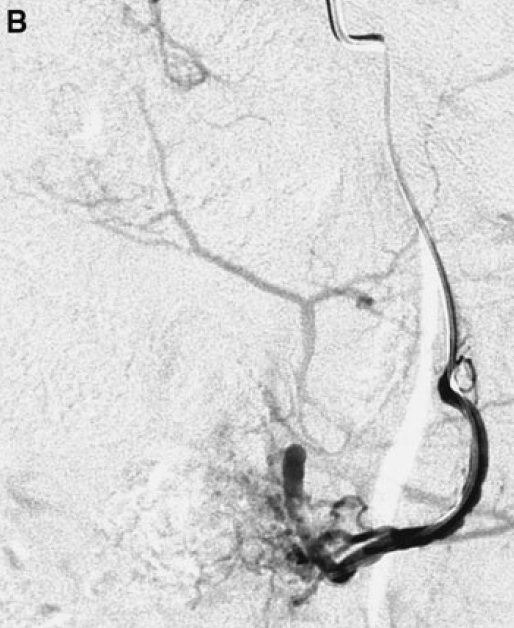

A Un artériogramme sélectif de l’artère utérine gauche. La position du cathéter était considérée comme légèrement trop proximale (l’extrémité au-dessus de l’origine des branches cervicovaginales) et a été corrigée pour l’embolisation.

B Contrôle final après instillation de 3,8 ml de microsphères Embozene de 500 micromètres. Le critère d’arrêt angiographique adéquat a été atteint (7).